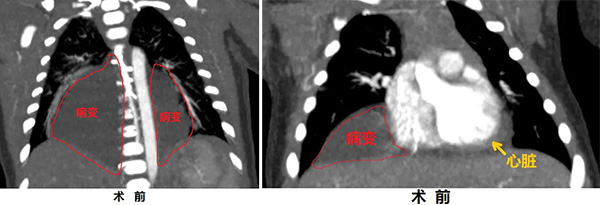

刘女士孕33周产检时发现胎儿有胸腔积液,孩子出生后在当地医院行胸部CT检查提示为纵隔占位,生后2天,患儿被紧急转运至北京儿童医院新生儿外科。影像学检查发现中后纵隔巨大占位,考虑为淋巴管畸形,肿瘤压迫心脏、包绕降主动脉,肺脏组织亦明显受压。面对这个肿瘤长在心脏旁且比心脏大的小患者,时间就是生命。

患儿14天时,石文媛主任为其进行了超声引导经皮淋巴管畸形注药治疗。术中,石文媛主任将一根纤细的治疗针精准置入瘤体内,随着病变体积的缩小,被压肺脏逐渐恢复了张力。治疗过程如同行云流水一气呵成,术中没有发生大出血、没有出现心肺功能障碍,手术顺利完成!由于采用了微创治疗技术,患儿平稳度过了术后危险期并迅速恢复,1周后小患者康复出院。超声引导注药治疗后3个月,经超声、核磁检查均发现,病变已基本消失。目前,16个月的小患儿发育良好,活泼好动,病变已完全消失。